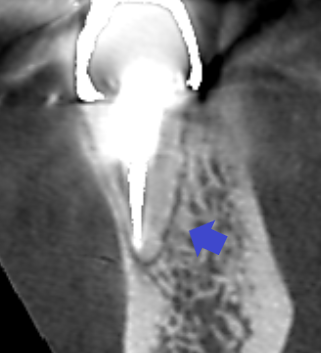

初診時の下顎第一大臼歯の矢状断のCT画像です。

矢印の先に膿の影がみられます。